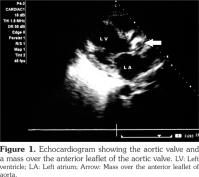

Cardiac involvement in granulomatosis with polyangiitis is rare. In this article, we describe a 47-year-old male case of aortic valve involvement with granulomatosis with polyangiitis. The patient had multi-system involvement in the form of pulmonary, renal, cutaneous involvement along with high levels of anti-proteinase 3. Echocardiography revealed a mass over the anterior leaflet of aortic valve with a mild aortic stenosis and aortic regurgitation. We suggest that clinicians should perform a thorough cardiac examination for any possible valvular involvement in patients with granulomatosis with polyangiitis.

The patient had normocytic normochromic anemia with a hemoglobin level of 8 g/dL, white blood cell count of 14000/mm3 with 80% neutrophils, serum urea value of 80 mg/dL, and serum creatinine value of 2.5 mg/dL. Serum electrolytes and liver function test results were normal. Urinalysis examination revealed protein 3+, and 15-20 red blood cells per high power field. Twenty-four-hour urine protein was 1.2 grams. Abdominal ultrasound revealed enlarged kidneys with increased echotexture and altered corticomedullary differentiation. Thoracic X-ray demonstrated bilateral pulmonary infiltrates, while computed tomography revealed bilateral patchy opacities with thickening of the right horizontal fissure and bilateral alveolar infiltrates. Echocardiography also revealed a mass over the anterior aortic valve with mild aortic stenosis and moderate aortic regurgitation (Figure 1). Anti-neutrophilic cytoplasmic antibody (ANCA) serology showed a markedly increased level of anti-proteinase 3 (anti-PR3) (31 IU/ml, cut off ≤3.5 IU/ml), and anti-myeloperoxidase (anti-MPO) level of 2.1 IU/ml (cut off ≤9 IU/ml). Blood cultures were sterile. Antinuclear antibodies, human immunodeficiency virus, hepatits B surface antigen, hepatitis C virus serologies and sputum for acid-fast bacilli were negative. A preliminary diagnosis of GPA with acute nephritis and probable alveolar hemorrhage were made based on the possibility of concomitant infective endocarditis/involvement due to GPA. The patient was firstly treated with broad-spectrum antibiotics. However, after three days of no response to the antibiotic therapy, the patient was started on pulse methylprednisolone doses of one gram per day for five days along with pulse cyclophosphamide of 750 mg, and the antibiotics were also continued. The patient improved over a period of one week, and his hemoptysis stopped. His repeat urea was 60 mg/dL, and serum creatinine level was 1.5 mg/dL. The patient was discharged with prednisolone 60 mg per day and was asked to apply to the outpatient department for the next pulse of cyclophosphamide. However, the patient did not report back and was lost to follow-up.

Our patient presented with predominantly renal and pulmonary involvement. Besides, in the course of investigation, he was found to have a valvular lesion in the form of aortic valve mass. We considered the possibility of the mass being a vasculitic lesion in view of the patient’s high disease activity in other organs including the lungs, kidneys and skin, and high titers of anti-PR3 antibodies. Additionally, no organism grew in blood cultures, and the patient responded to high doses of parenteral steroids.

Thus, we report a very rare occurrence of an aortic valve mass in a patient of GPA which we presume to be a lesion secondary to GPA. The pointers in favor of the mass being secondary to GPA were (i) having no response to initial antibiotic therapy, (ii) sterile blood cultures, and (iii) pulmonary involvement in the form of pulmonary hemorrhage and hemoptysis. Also, the patient responded to the immunosupression rather than deteriorating which would have been the case if the patient had underlying subacute bacterial endocarditis and sepsis. However, our report is limited by the fact that the patient was lost to follow-up. Besides, the histopathology of the mass lesion was not available. We believe that all the patients with GPA need to undergo echocardiography for any cardiac involvement.